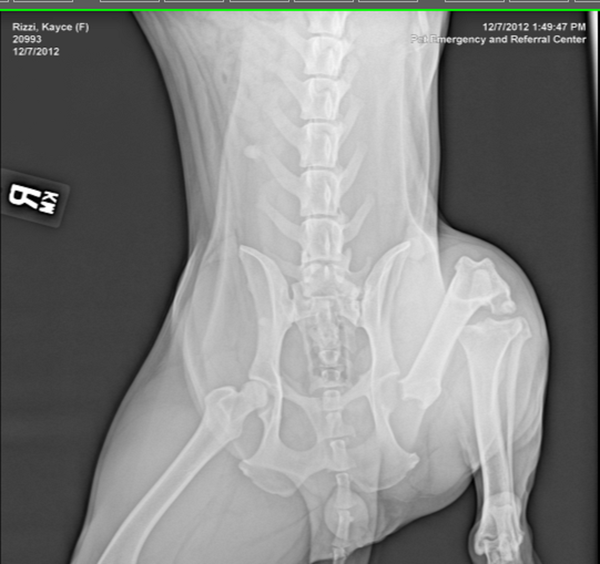

Hey guys, wanted to throw this up here and see if anyone is willing to donate a few bucks to help us out. Long story short, but buddies dad heard a dog crying from a few houses down, went out looking to see what was going on. Walked into someones back yard and caught the owner of the dog beating her with a steel hammer. Needless to say, he took the dog to the animal hospital where the prognosis was a severely fractured hip as well as a few other issues.

He kept the dog and had the former owners sign her over. After a few trips to the surgeons office, the say she needs a full hip replacement to be able to live a full life. The entire story as well as x-rays, the prognosis and recommendations from the surgeon are on the donation page.